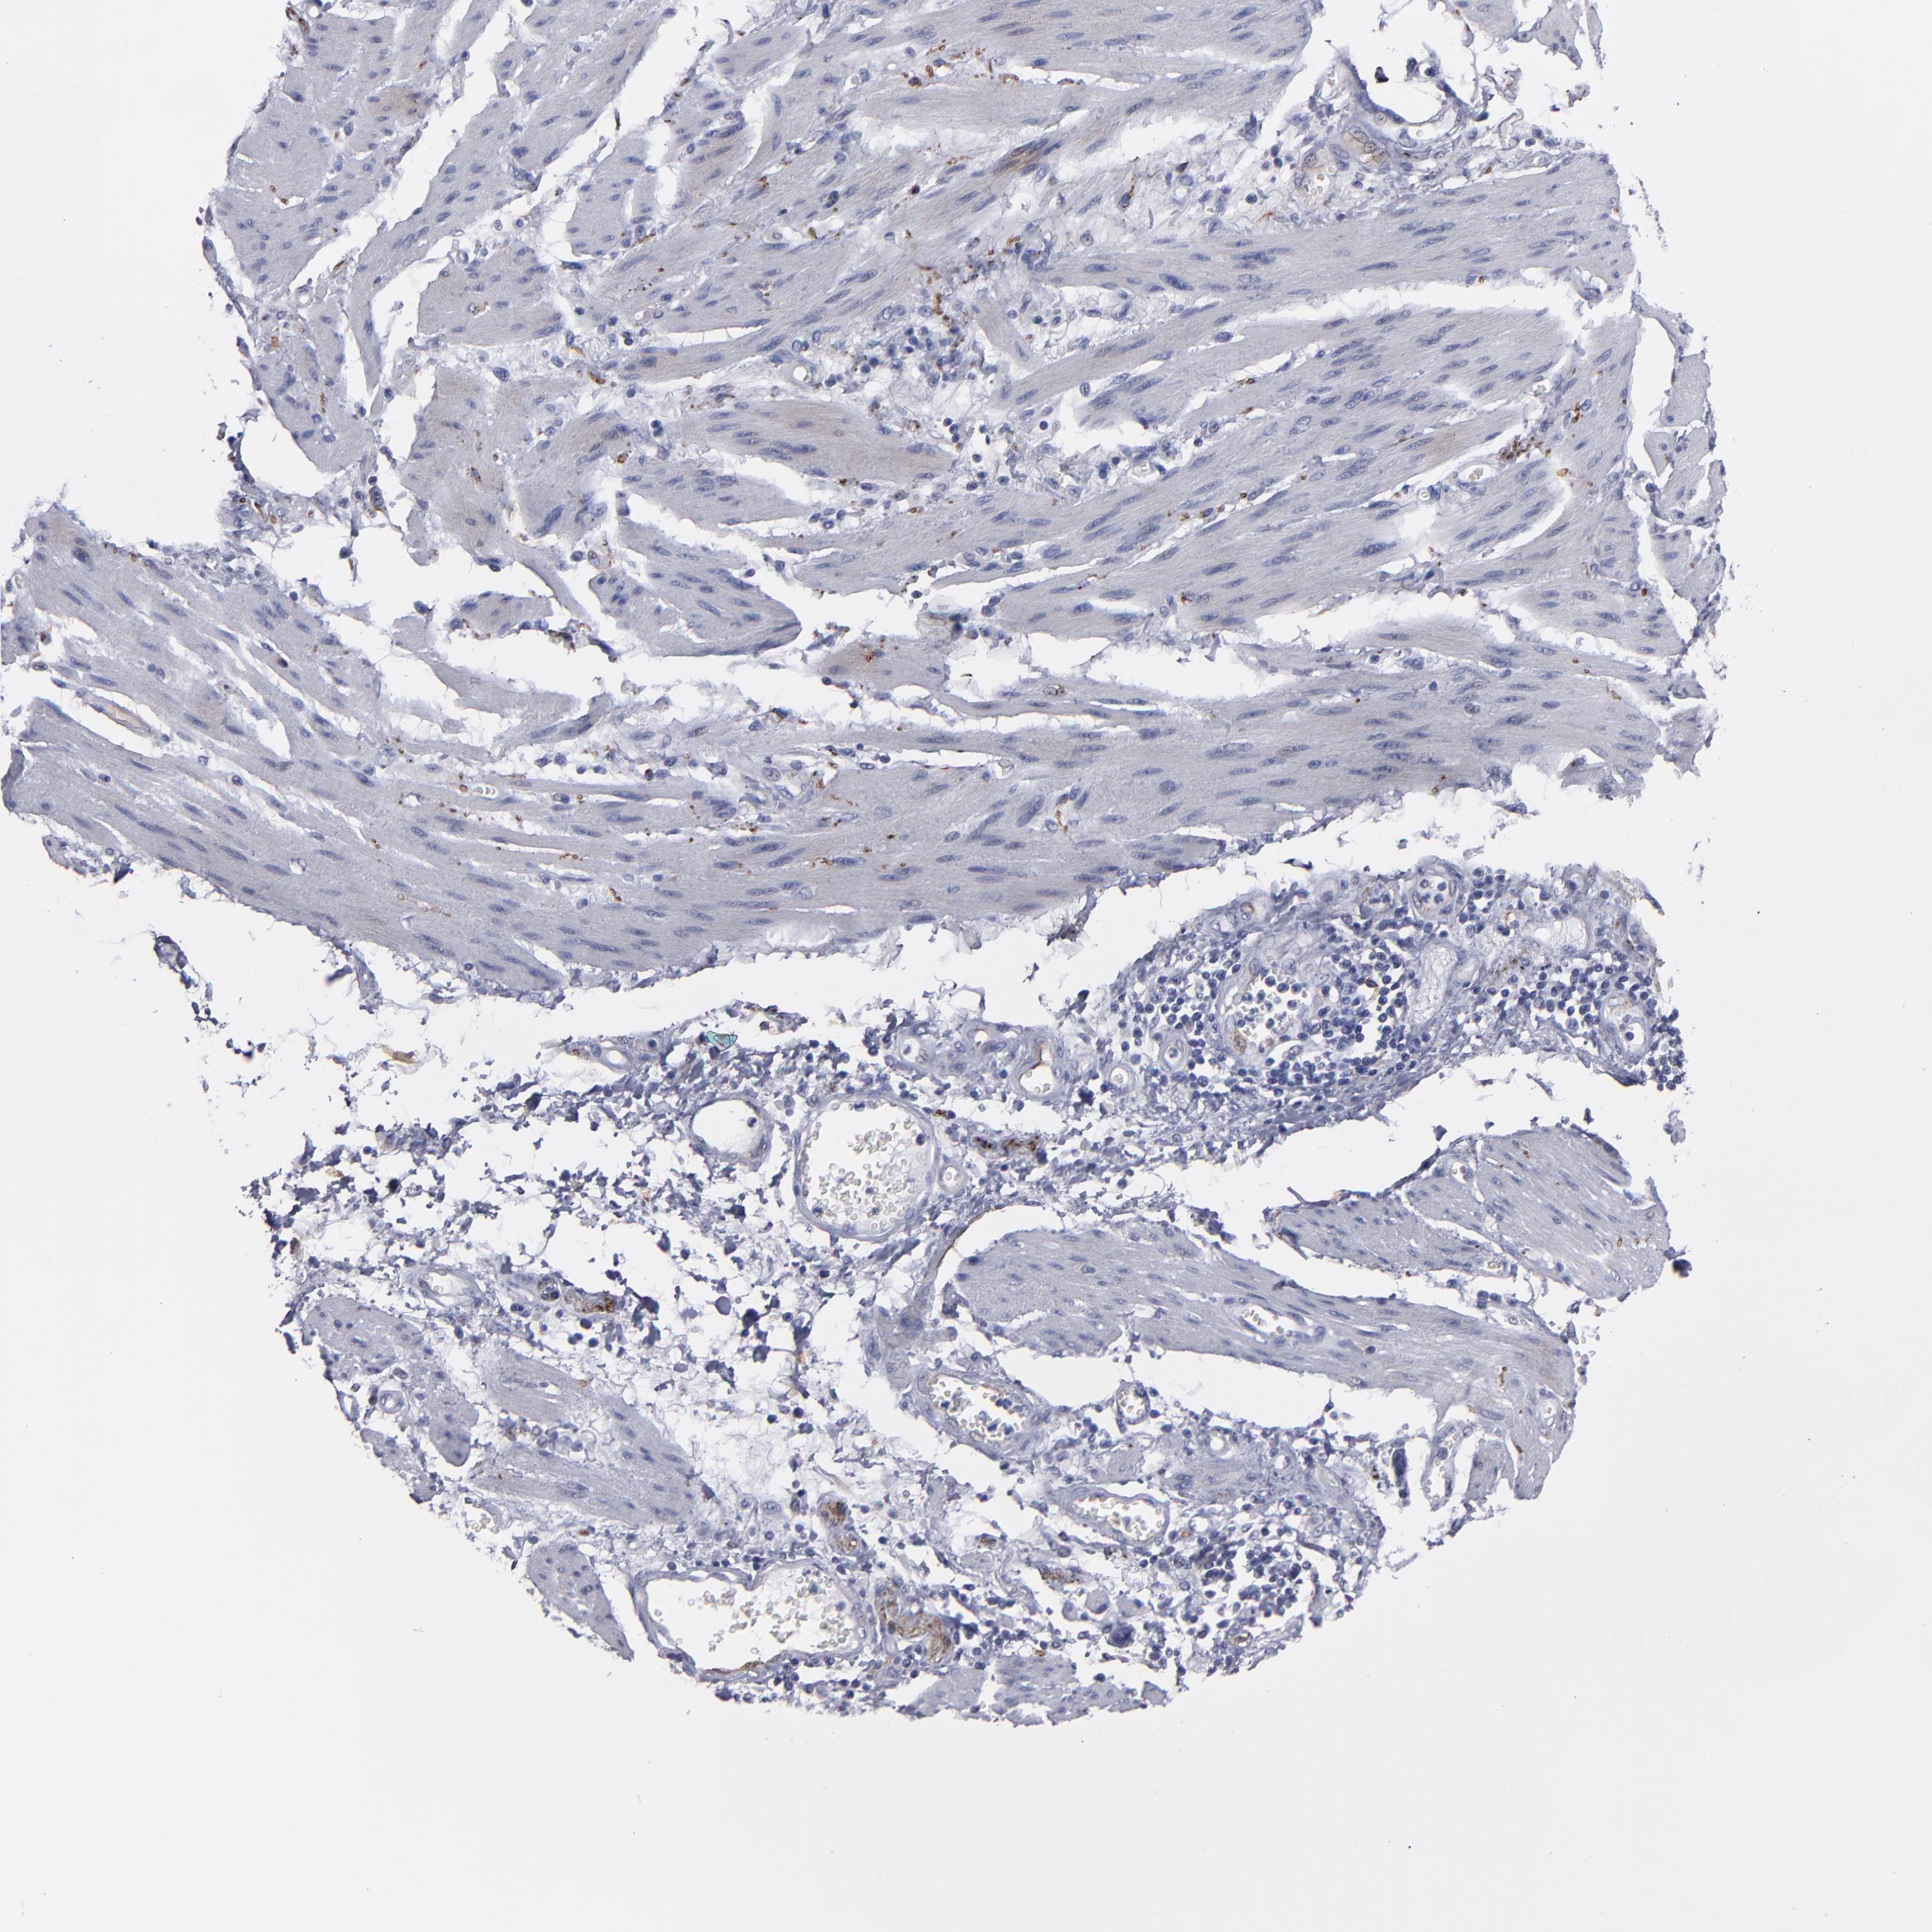

STOMACH CANCER - Protein expressioni

A mouse-over function shows sample information and annotation data. Click on an image to view it in a full screen mode. Samples can be filtered based on level of antibody staining by selecting one or several of the following categories: high, medium, low and not detected. The assay and annotation is described here.

Note that samples used for immunohistochemistry by the Human Protein Atlas do not correspond to samples in the TCGA dataset.

Antibody stainingi

Antibody staining in the annotated cell types in the current human tissue is reported as not detected, low, medium, or high, based on conventional immunohistochemistry profiling in selected tissues. This score is based on the combination of the staining intensity and fraction of stained cells.

Each image is clickable and will lead to virtual microscopy that enables deeper exploration of all samples and also displays staining intensity scores, fraction scores and subcellular localization as well as patient and tissue information for each sample.

Antibody HPA002981

Antibody CAB025746

Staining

High

Medium

Low

Not detected

Adenocarcinoma, NOS

Adenocarcinoma, High grade